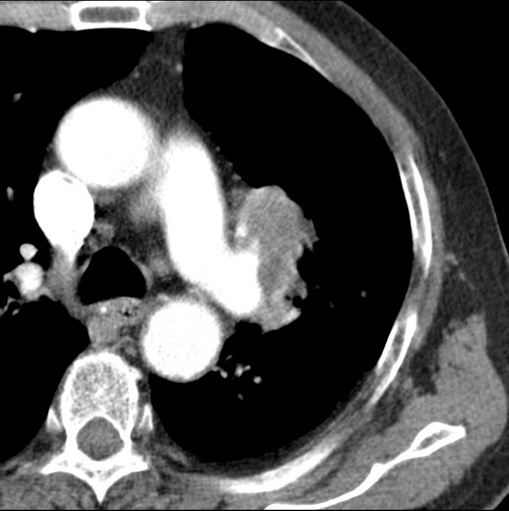

标题: CT25434:胸部CT增强扫描

男性患者 81岁 咳嗽 咳痰 咯血

有强化 考虑肺癌肺门淋巴结转移

肿块贴近左肺门,包绕左上肺动脉,形态不规则。肿块增强扫描中度强化。纵膈内主动脉弓左旁间隙、气管隆突前、下间隙见多枚淋巴结影。综上考虑左侧中央型肺癌可能性大。图片没有完整上传,尤其是左肺上叶支气管分支层面没有上传,因此不好判断是叶支气管中断还是段支气管中断。另外,下图红色部分所示是“黏液支气管征”吗?